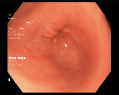

4.1.7 Gastrointestinal endoscopy

Endoscopies are used to detect diseases in the human digestive system. Images from inside the gastrointestinal tract can help physicians detect diseases early. The used dataset 777https://www.kaggle.com/datasets/abdallahwagih/kvasir-dataset-for-classification-and-segmentation contains eight image categories of the digestive system obtained through the endoscopy imaging technique, as shown in Fig. 8. There are a total of images that can be used in training and testing ML algorithms.